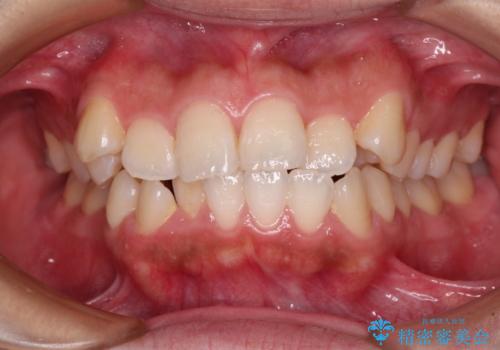

- 前歯の出っ歯と口元の閉じにくさを気にして来院された患者様です。

口元を積極的に引っ込めるために、上下左右の小臼歯4本を抜歯することとしました。

4本の歯を抜歯したことで、飛び出していた口元が引っ込み、横顔の印象が大きく改善されました。